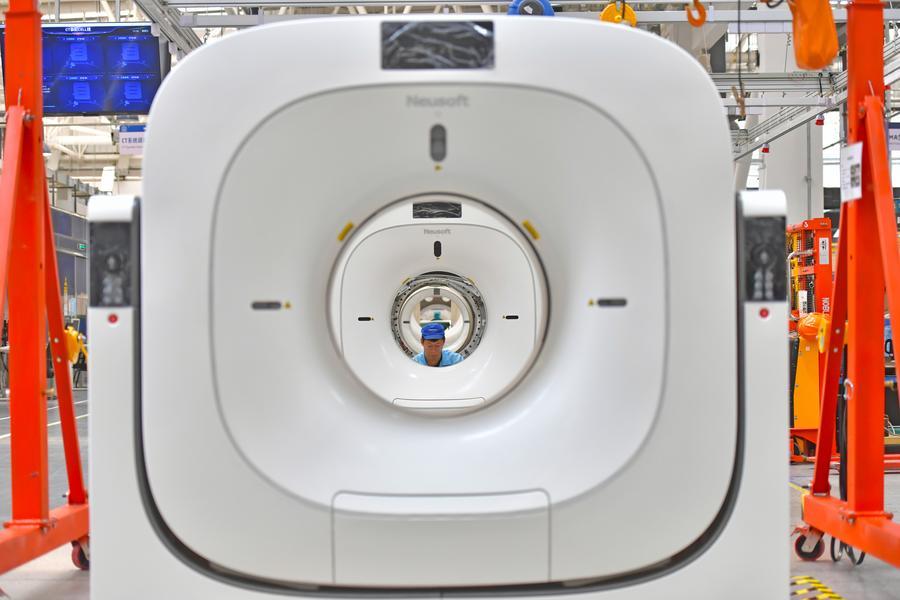

Beijing, 19 jan (Xinhua) -- Uma nova onda de medicamentos e dispositivos médicos fabricados na China está chegando ao mundo, destacando os grandes passos que a China deu no mercado global de saúde.

Produtos tradicionais de forte desempenho, como ingredientes farmacêuticos ativos químicos e dispositivos médicos, mantiveram uma grande participação no mercado global, enquanto suas escalas de exportação aumentaram de forma constante, de acordo com a pasta.

As exportações de produtos farmacêuticos e dispositivos médicos da China estão avançando constantemente em direção a setores de maior valor agregado, com medicamentos inovadores, formulações de ponta e dispositivos médicos de alto desempenho se tornando o foco, de acordo com autoridades que participaram de uma conferência realizada pela Administração Nacional de Seguridade de Saúde no sábado, em Beijing.